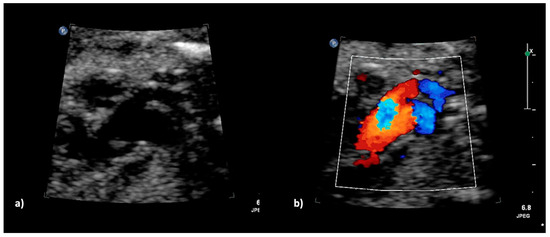

Figure 2.

(a–c): Truncus arteriosus type 1 at 22 + 0 weeks in B-mode (a,b) und with color doppler (c).